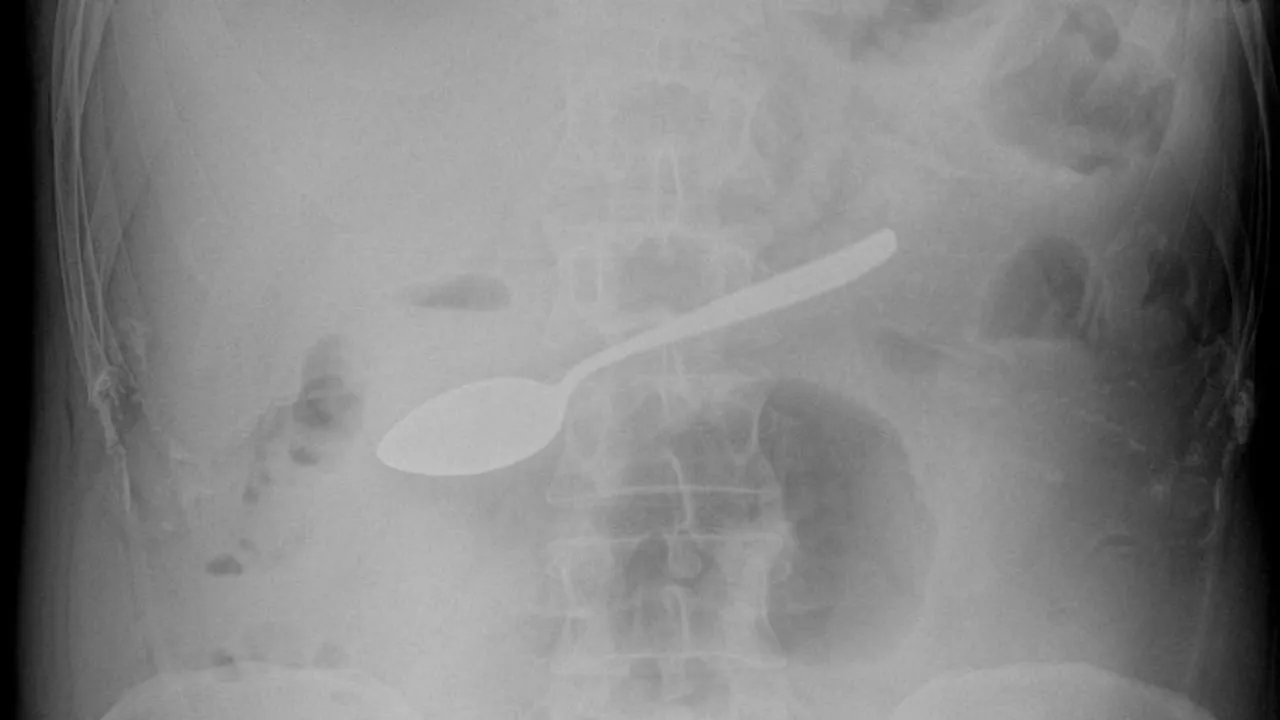

Врачи Мытищинской больницы оказали помощь мужчине, который случайно проглотил десертную ложку. По информации Министерства здравоохранения Московской области, инцидент привел к угрозе внутреннего кровотечения.

42-летний житель города Мытищи был экстренно доставлен в больницу с симптомами тошноты и рвоты. В ходе медицинского обследования специалисты обнаружили в его желудке инородное тело — маленькую ложку.

Как отметил эндоскопист больницы Максим Щипачев, если крупный металлический предмет не будет вовремя извлечен из пищеварительного тракта, это может привести к серьезным последствиям, включая внутреннее кровотечение, что в свою очередь может иметь летальный исход. Известно, что такой предмет не может выйти естественным путем.

В связи с критической ситуацией мужчину срочно прооперировали. С помощью современного эндоскопического оборудования медицинские специалисты смогли извлечь ложку через пищевод. Операция была сложной из-за формы предмета, однако, в конечном итоге, прошла успешно. На данный момент пациент уже выписан из больницы и чувствует себя хорошо.